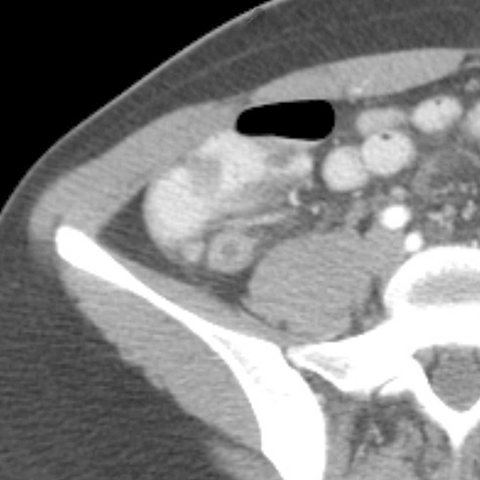

18 year-old male presents with a sudden onset of RLQ pain and rebound tenderness. [3 of 5]